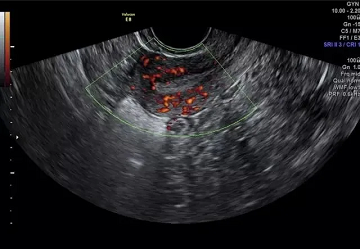

3、子宫内膜血流

子宫内膜接受胚胎种植需要丰富的血流,子宫动脉血流用搏动指数(PI)和阻力指数(RI)表示。

.png)

研究表明,PI能够预测妊娠结局,当PI<2时,ER最好。虽然PI值反映了整个子宫的血流,但是子宫和卵巢血管之间存在交通支,因此子宫动脉的PI值不能准确反映内膜组织血供。